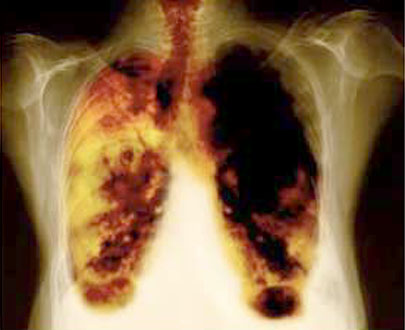

La oncóloga Angélica Cruz Cadena informó que de acuerdo con el más reciente reporte epidemiológico México registró en el último año ocho mil casos nuevos de cáncer de pulmón, enfermedad que a nivel mundial representa de las neoplasias más agresivas por el alto grado de mortalidad que tiene.

'Durante el último año se presentaron alrededor de ocho mil nuevos casos de cáncer de pulmón, entre los que predomina un tipo de cáncer llamado de células no pequeñas, con 80 por ciento de los pacientes', precisó.

Explicó que este tipo de cáncer de pulmón de células no pequeñas es de los principales asesinos en materia de neoplasias, por lo que la ciencia se ha enfocado en encontrar alternativas cada vez más eficaces para combatirlo.

Informó que en diversos países del mundo el cáncer de pulmón es el que más muertes ocasiona, puesto que mata a un millón 380 mil personas al año, más que los cánceres de mama, próstata, colon, hígado, riñón y melanoma juntos.